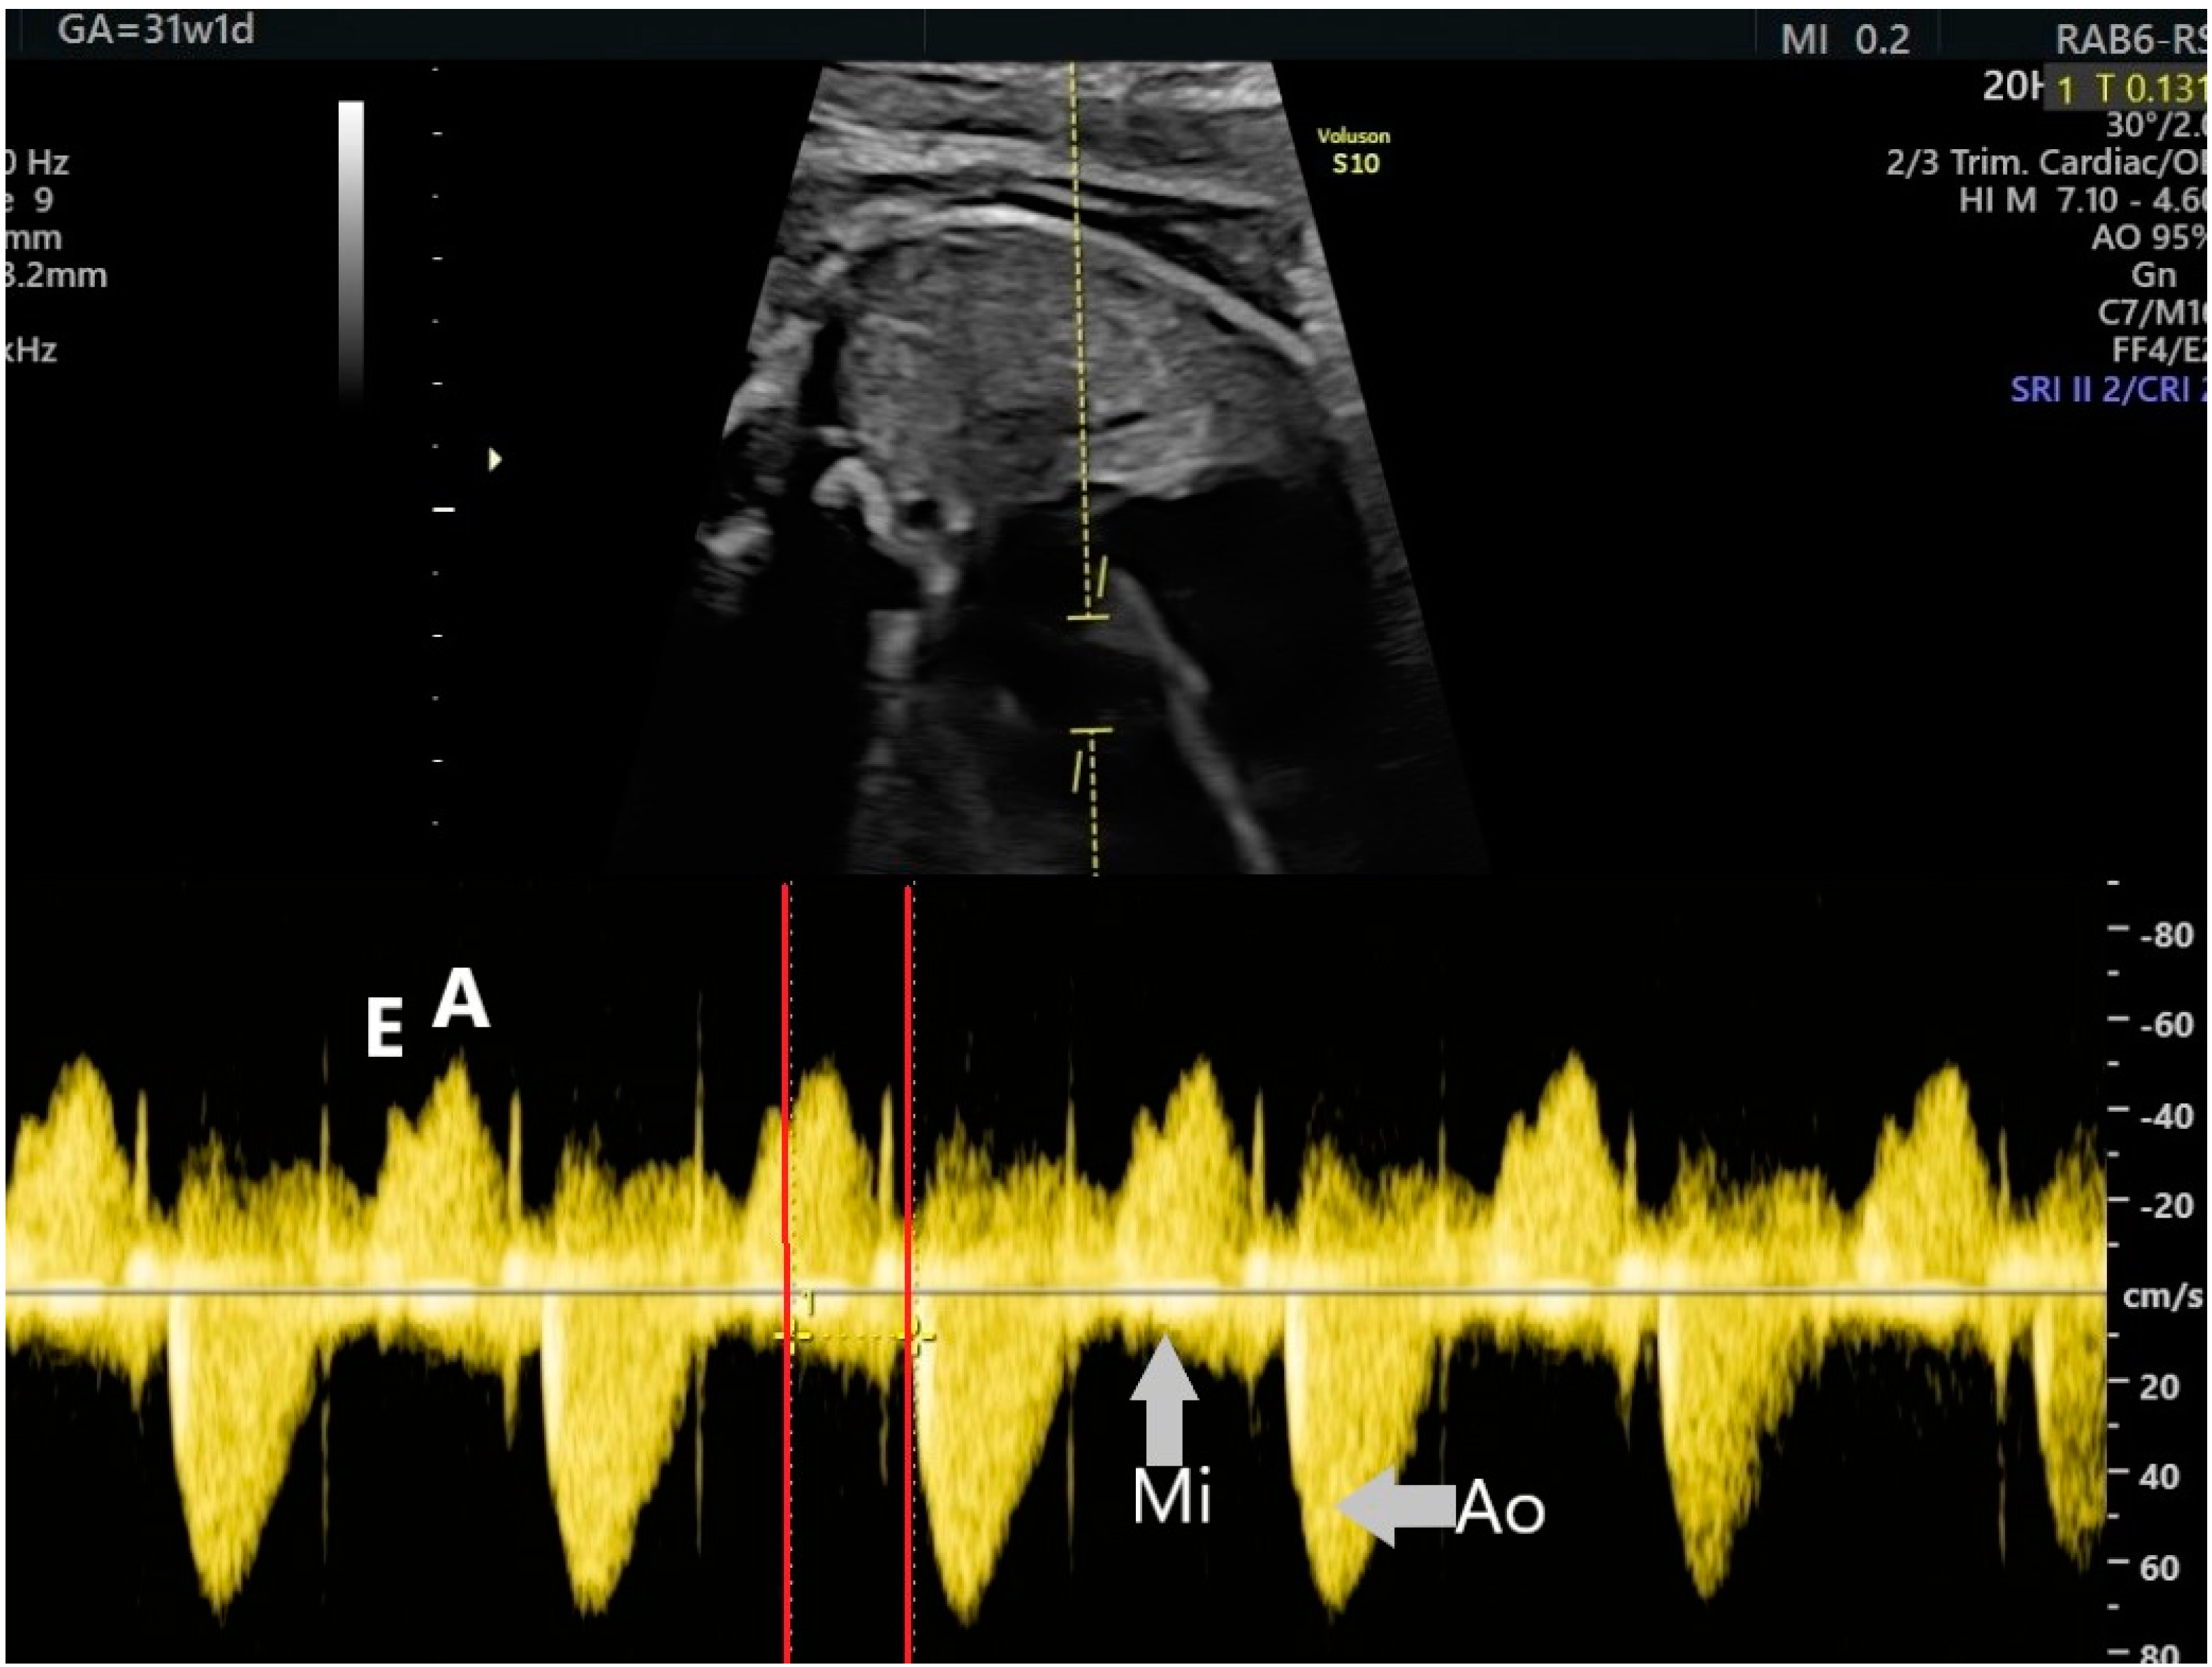

2. The Use of Ultrasound to Assess Fetal Heart Rhythm